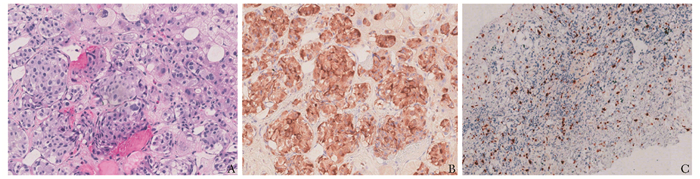

• 摘要: 恶性胰岛素瘤是疑难罕见的神经内分泌肿瘤之一,常合并远处转移,其中以肝转移最常见,预后多不佳。本文报道1例恶性胰岛素瘤多发肝转移病例。患者男性,70岁,因“发作性意识障碍4个月余”入院,监测血糖发现其空腹、餐后及夜间均反复出现低血糖。胰腺灌注CT及肝脏动态增强MRI发现胰头钩突部占位、肝内多发转移灶,经皮肝穿刺活检病理证实为胰岛素瘤。经多学科讨论后,分期行肝内动脉介入栓塞及射频消融治疗,同时联合依维莫司治疗。复查增强CT可见部分肝转移灶缩小。患者规律加餐,血糖逐渐上升并维持在正常水平。本文讨论该病例的临床特征及多学科协作诊疗经过,旨在为恶性胰岛素瘤患者的临床综合诊治提供经验。

Abstract: Malignant insulinoma is a kind of rare and challenging neuroendocrine tumor. It is often accompanied by distant metastasis, among which liver metastasis is most common, and the prognosis is often non-promising. In this paper, we report a case of multiple liver metastases from malignant insulinoma. The patient, a 70-year-old male, was admitted to the hospital due to "episodic consciousness disorder for more than four months." Blood glucose monitoring revealed recurrent hypoglycemia in the early morning, after meals, and at night. Pancreatic perfusion CT and dynamic enhanced MRI of the liver revealed a mass in the uncinate process of the pancreatic head and multiple liver metastases. Percutaneous liver biopsy confirmed the diagnosis of insulinoma. After multidisciplinary discussions, hepatic artery embolization and radiofrequency ablation were performed in stages, in combination with everolimus treatment. Thereafter, the enhanced CT demonstrated that some liver metastases shrank. The patient had regular meals, and the blood sugar gradually increased and remained normal thereafter. This article discusses this case's clinical characteristics and multidisciplinary collaborative diagnosis and treatment, aiming to provide experience for the comprehensive clinical diagnosis and treatment of malignant insulinoma patients.